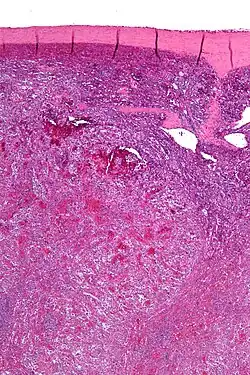

Low magnification micrograph of a littoral cell angioma. H&E stain. | |

Littoral cell angioma, abbreviated LCA, and formally known as littoral cell angioma of the spleen, is a benign tumour of the spleen that arises from the cells that line the red pulp.[1]

Littoral cell angiomas show in CT scans. They are diagnosed by pathologists by taking a sample of the tumour via Fine Needle Aspiration or Core Needle Aspiration or from a splenectomy. Histologically, they have anastoming small vascular channels and cystic spaces with papillary projections.[2]